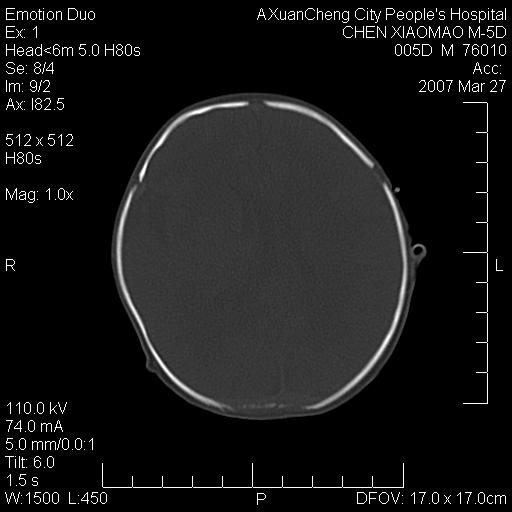

大家看看可有出血?另外枕骨中央是骨缝还是骨折

颅内未见明显异常。枕骨鳞部应为假缝(颅外软组织无肿胀),有外伤吗?

大家看看可有hie ?还有左侧枕部胡形高密度ct为45~53hu,可有硬膜下血肿?

左颞枕部有出血,枕骨有骨折

枕骨骨折可以下,应该比较明显,颅内还是正常的,不放心的话,短期随访。

未见明显异常,,那是横窦影,“缝”是后囟